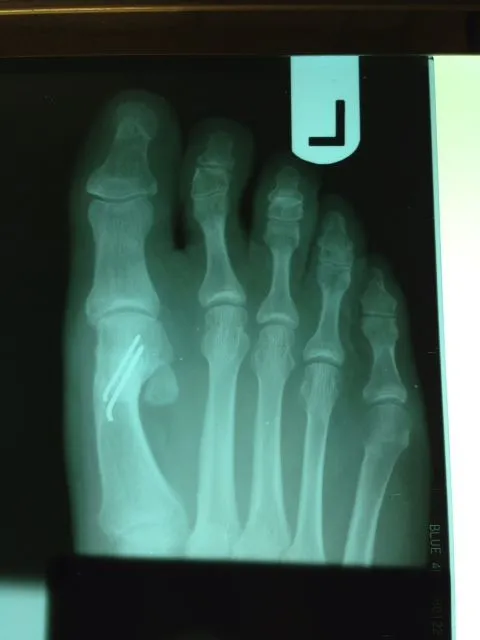

Before and immediately postop S/P bunionectomy

Before and 6 months status post bunionectomy.